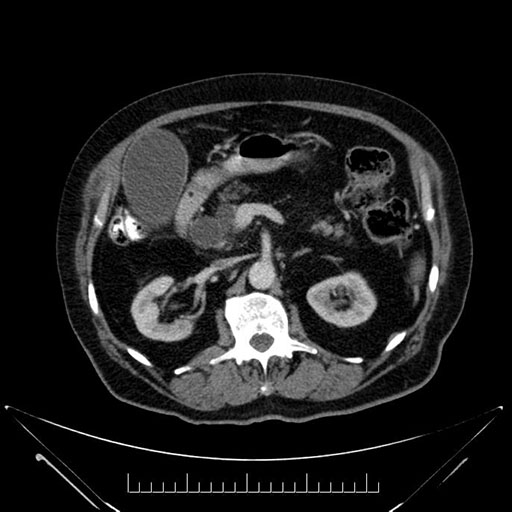

Axial - 3 months prior